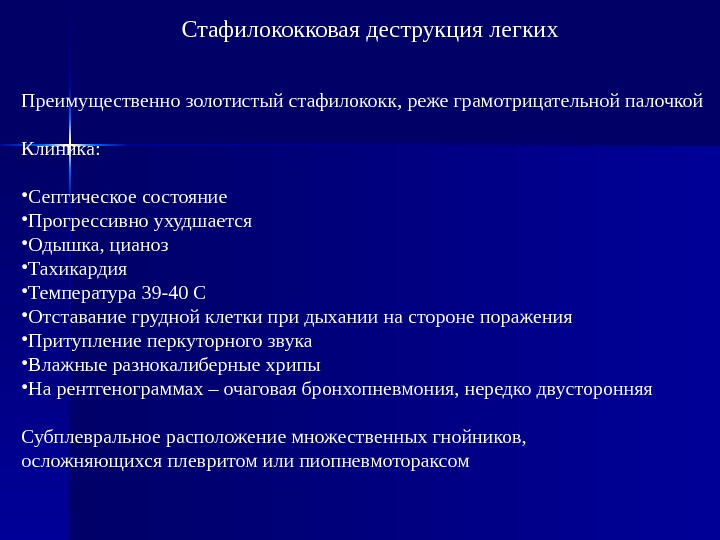

Бактериальная деструкция легких у детей презентация - 88 фото